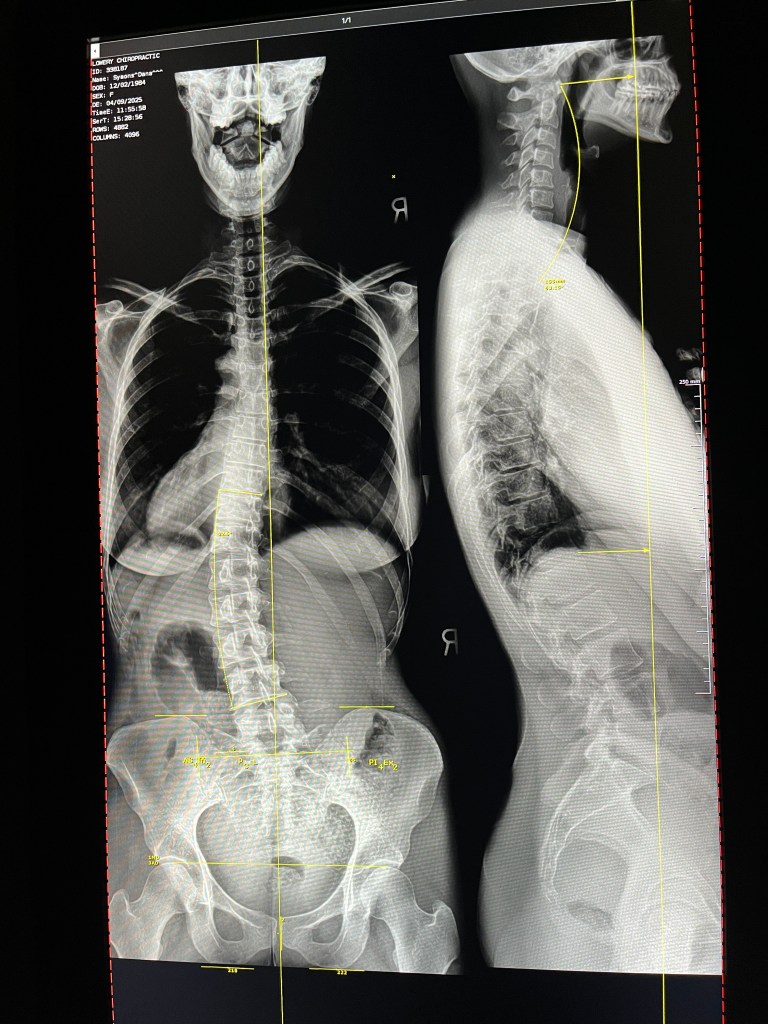

That got me thinking. I’ve been hearing a lot about burnout lately, perhaps even feeling burnt out myself. When you lack energy and motivation to do the things you’re doing, it should give you pause. What are those symptoms telling you? I agree with the second half of the pastor’s statement, but I think it deserves some exploration. I think burnout is a real thing — but it makes sense to me that it’s something we experience when we are somehow misaligned with God’s will. I said that to the chiropractor with no pun intended, but since that was the context, let’s go with that analogy. The spine is your lifeline, or so I have heard it said. It is critical both structurally and functionally for the rest of your body. When it’s out of alignment, you feel pain, weakness, numbness, stiffness, inflexibility or any number of other ailments that may stem from the compression of nerves. What happens when we are out of spiritual alignment? Perhaps depression, fatigue, lack of motivation, hopelessness, the feeling that something is missing or even physical and emotional pain from the consequences of our choices.